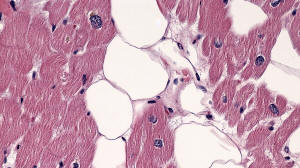

Figure E. H&E x20

Histology: H&E staining (Figures C-F) from the explanted heart shows patchy replacement of the myocardium by adipose tissue.